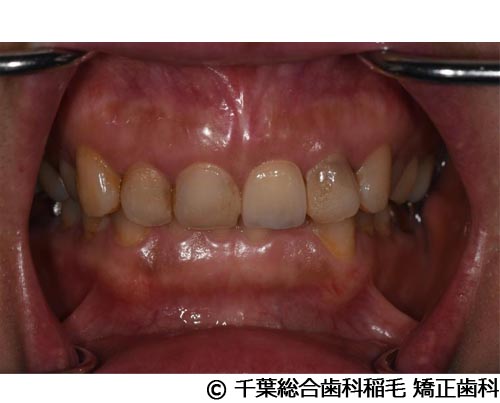

【症例4】上顎前歯1本インプラント埋入手術

- 治療前

- 治療後

- 治療名

- 上顎前歯1本インプラント埋入手術

- 費用

- 600,000円(税込)

- 期間

- 11ヵ月

治療内容

患者様の症状

前歯の色味が気になりご来院されました。

治療法

根っこが割れていたため抜歯となりました。

インプラント、ブリッジ、義歯それぞれのメリット、デメリットをお話させていただき、インプラントでの治療を選択されました。 -

治療結果

機能性、審美性ともに改善し、満足していただけました。

現在も定期検診で拝見させていただいています。